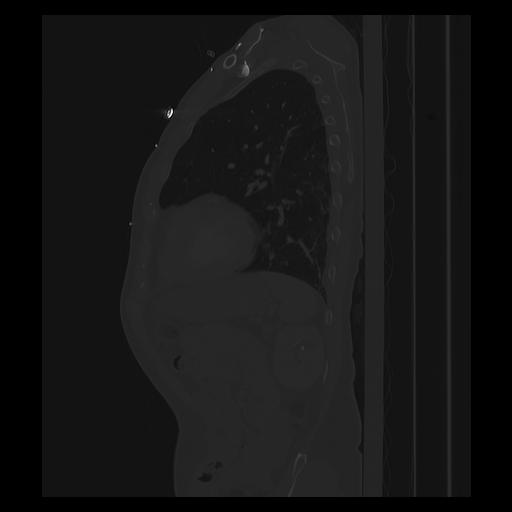

33 PULMON,CE,Sagittal,3.000,PULMON,Sagittal,